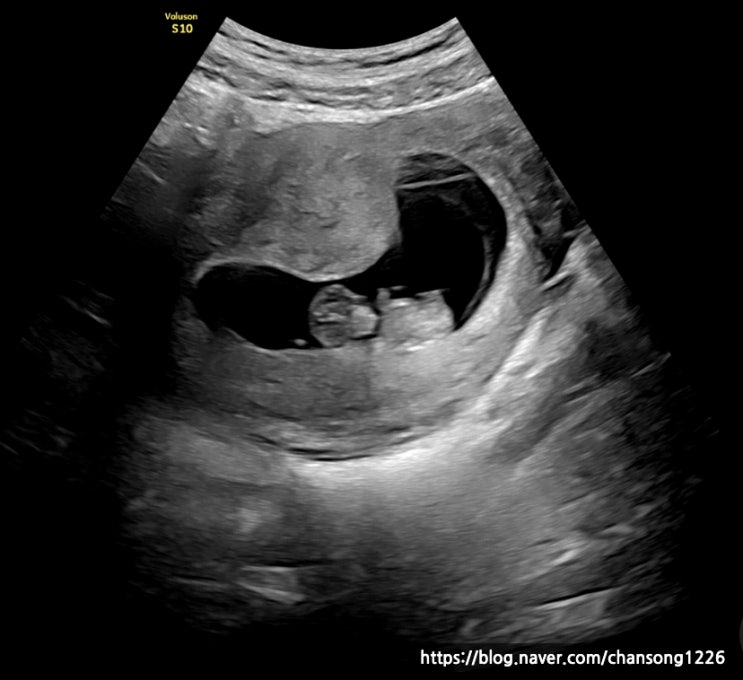

임신중기 12주 15주 16주 초음파 성별확인 1차 기형아 검사 태동시기

저의 임신중기 초음파와 증상에 대해 기록하고자 합니다. 성별확인과 1차 기형아 검사, 그리도 태동에 대한...

임신초기 7주 8주 9주 임신증상 및 입덧과 초음파

사람마다 주수별 임신 증상은 천차만별이겠지만 저의 경우의 임신증상에 대해서 기록해 보고자 합니다. 전...